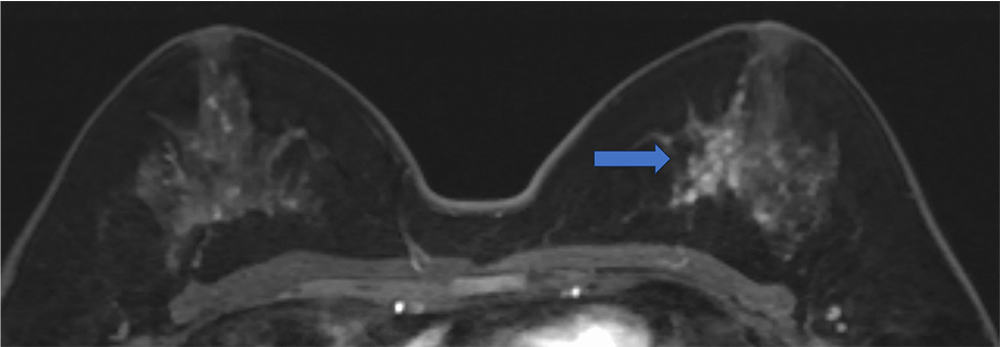

5. Ultrafast DCE 造影剤投与約20秒後、23秒後、26秒後

BPEが目立たないため、左乳房内側の病変が容易に同定できる

ultrafast MRI 造影剤投与

約26秒後